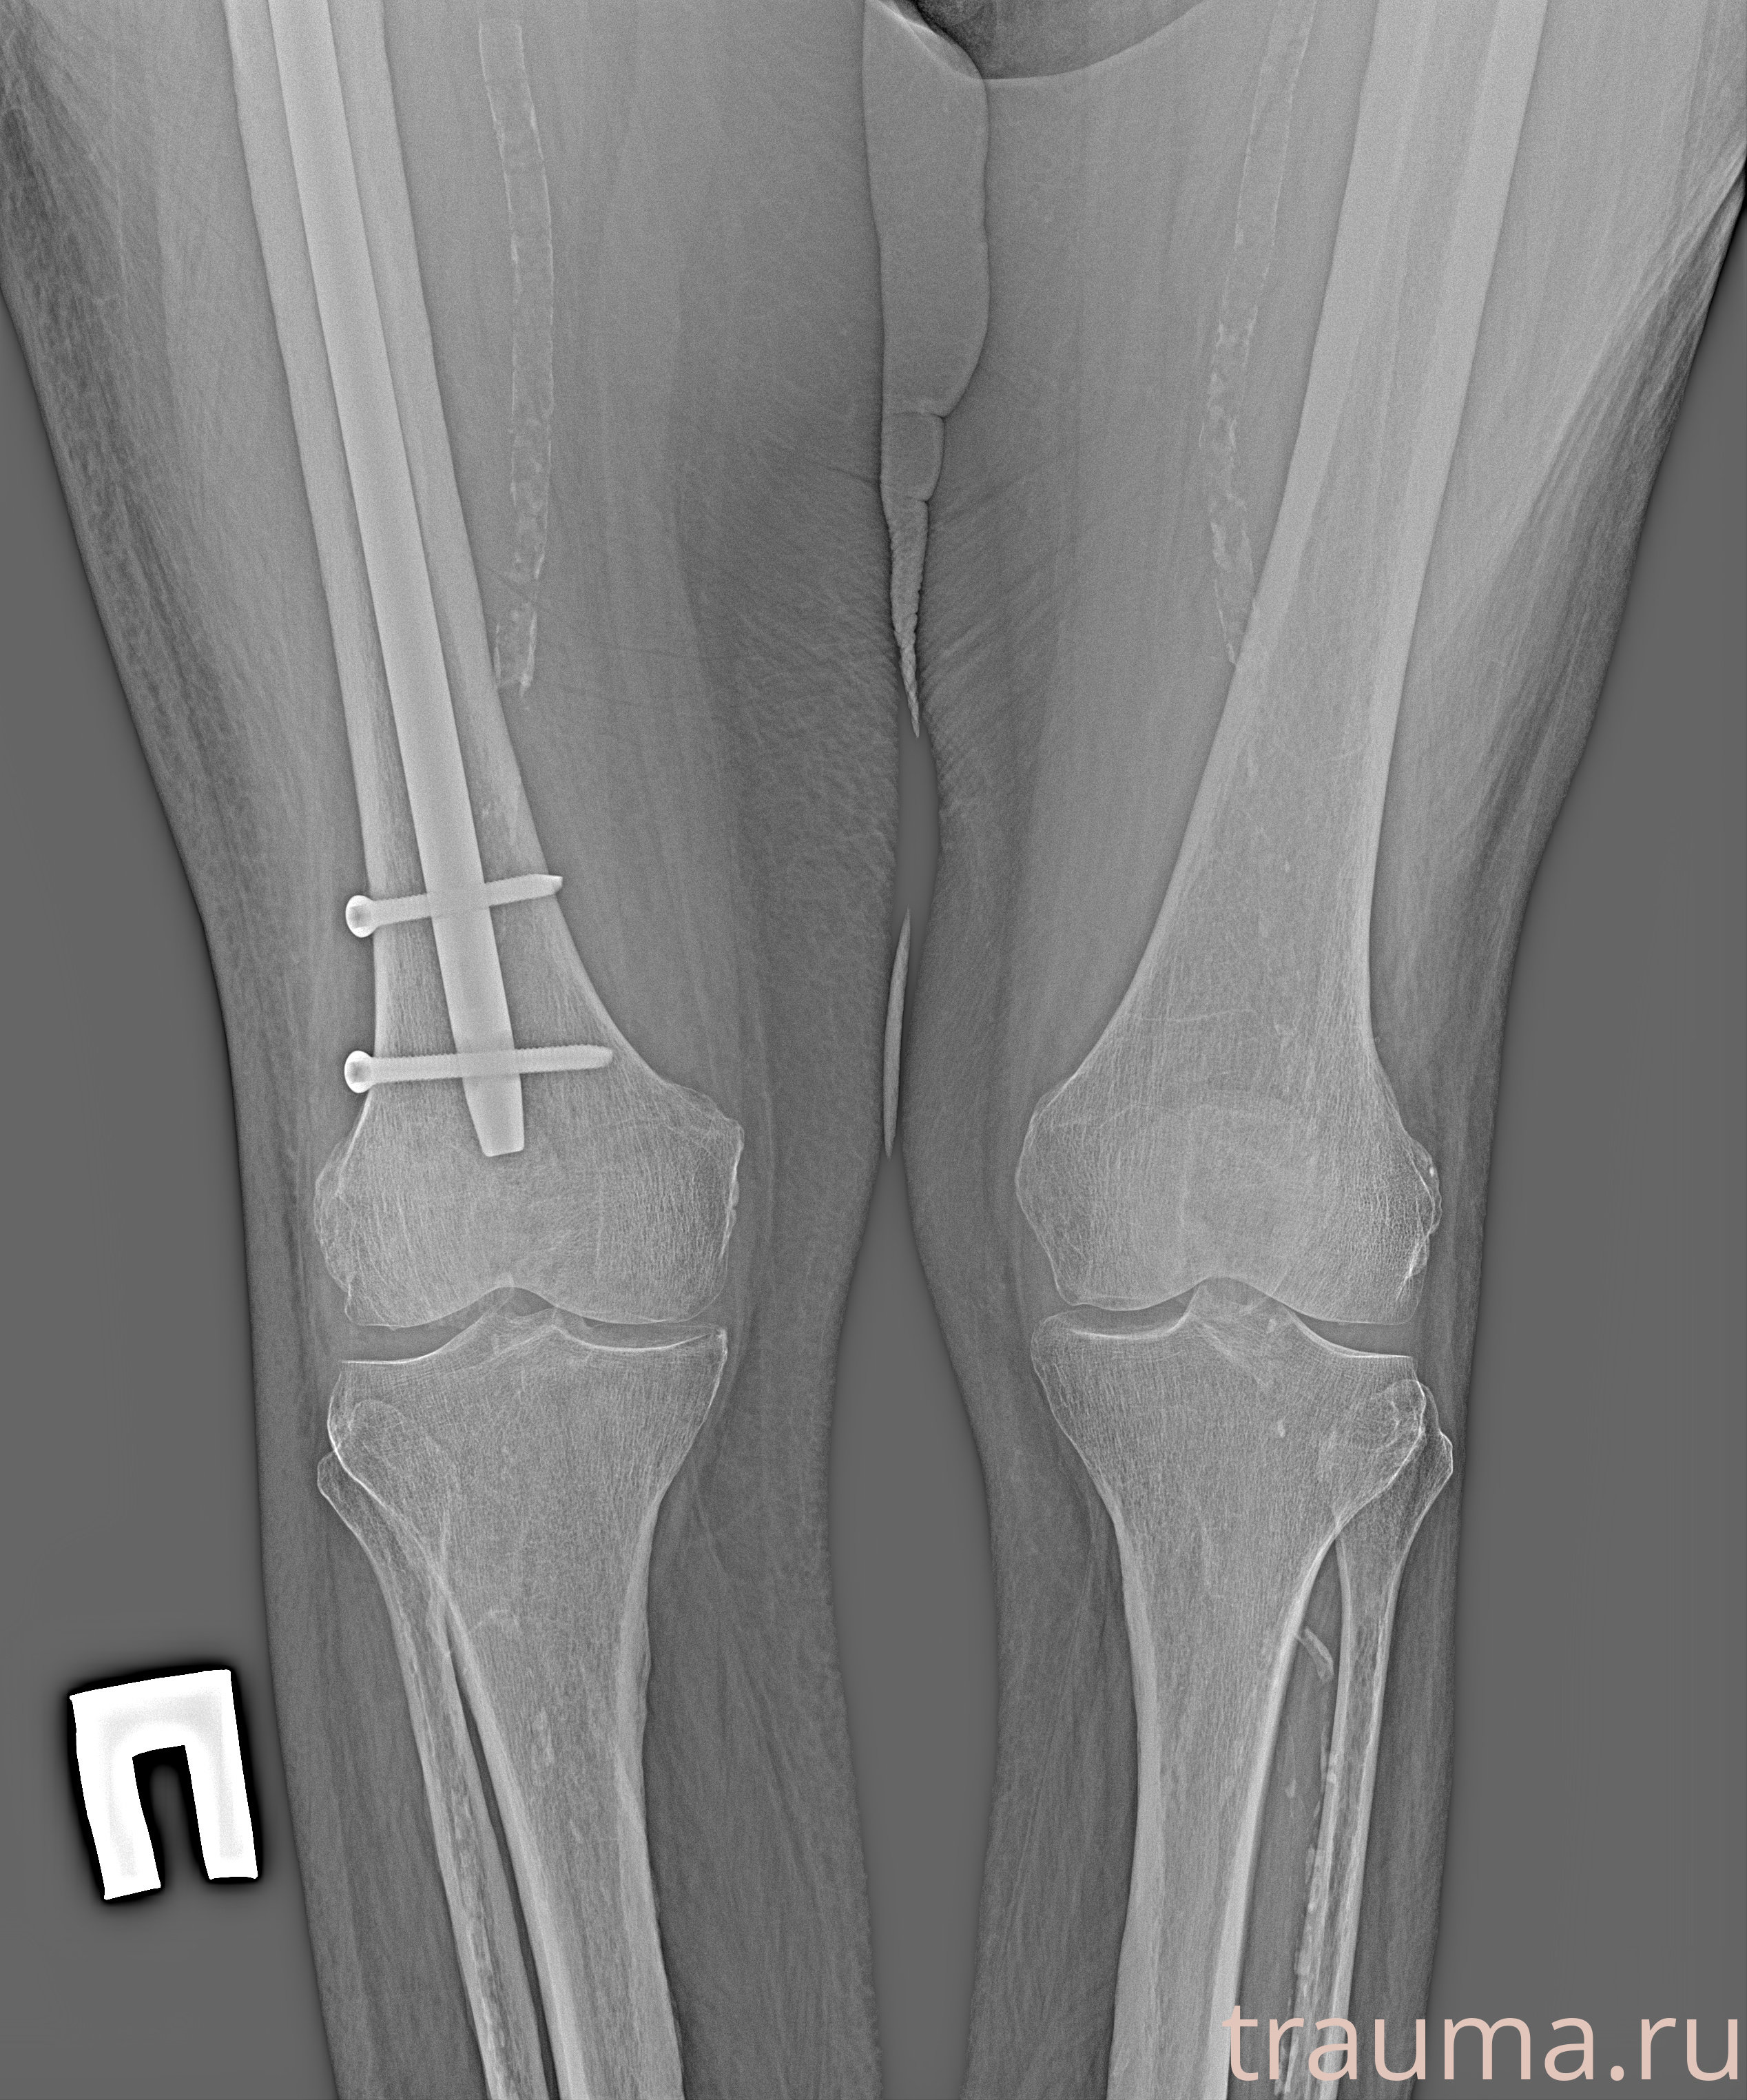

Рентгенограммы

Рентген на дому: по вашему адресу приезжает врач-рентгенолог, травматолог-ортопед с мобильным рентгеновским аппаратом, проводит диагностику травмы или заболевания, делает необходимые рентгенограммы, дает рекомендации по дальнейшему лечению. Получить качественные снимки в домашних условиях возможно благодаря уникальной методике, разработанной МосРентген Центром для института  Склифосовского